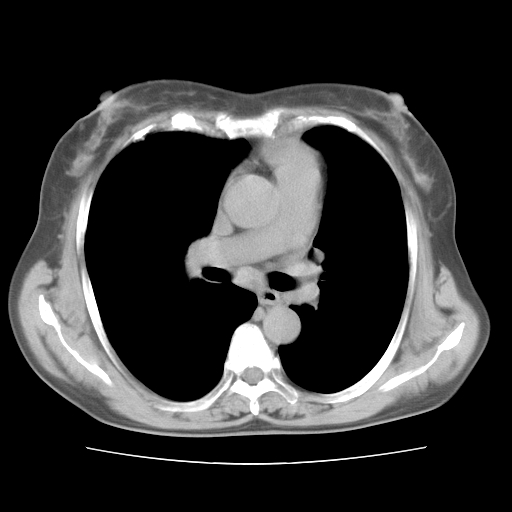

标题: CT10838:女性,56岁,是上腔静脉钙化还是淋巴结钙化?

女性,56岁临床诊断为胃贲门ca,术前检查发现,此钙化灶,对此科内稍有争论!请各位老师看看!是上腔的还是淋巴结的?有意义吗?

淋巴结钙化,上腔静脉在外侧可看到.

支持淋巴结钙化,气管前胸骨后也有.

胸锁关节层面的是淋巴结钙化,气管前腔静脉后的钙化灶占了4个层面,不知层厚是多少?看样子应该是7--10毫米之间,那么这病灶最小纵径得有28毫米!应该提示点什么了,没传肺窗,估计肺内没有病变?

左锁骨下静脉和头臂静脉会合后形成是上腔静脉,此钙化位于两血管回合的腔静脉后方、气管右前方,这个位置没有其他结构,应该是淋巴结钙化。一般多为淋巴结核后钙化,没有临床意义。